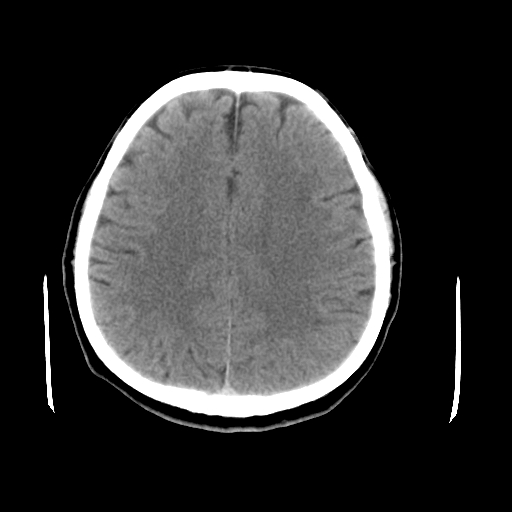

以下是引用liuyue在2008-4-28 13:34:00的发言:[br]右额叶条状高密度影,边缘清楚,周围未见水肿及占位.[br]考虑:血管畸形可能性大.[br]建议:强化ct扫描或mri检查.除外脑回钙化.

以下是引用论黑辩白在2008-4-28 12:53:00的发言:[br]右额叶局限性脑萎缩,右额叶见条状高密度影,建议mri进一步检查。[br][br][本贴已被 论黑辩白 于 2008-4-28 13:08:16 修改过]